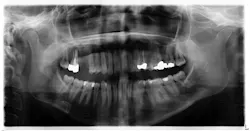

Six years later (the patient left the area and then returned), the patient presented to my office for updates with a chief complaint of caries on her wisdom teeth and a desire to have them removed. A new panoramic radiograph was taken. The lesion on the lower right side of the mandible was noted as still present with no significant changes in shape or size (figure 2).